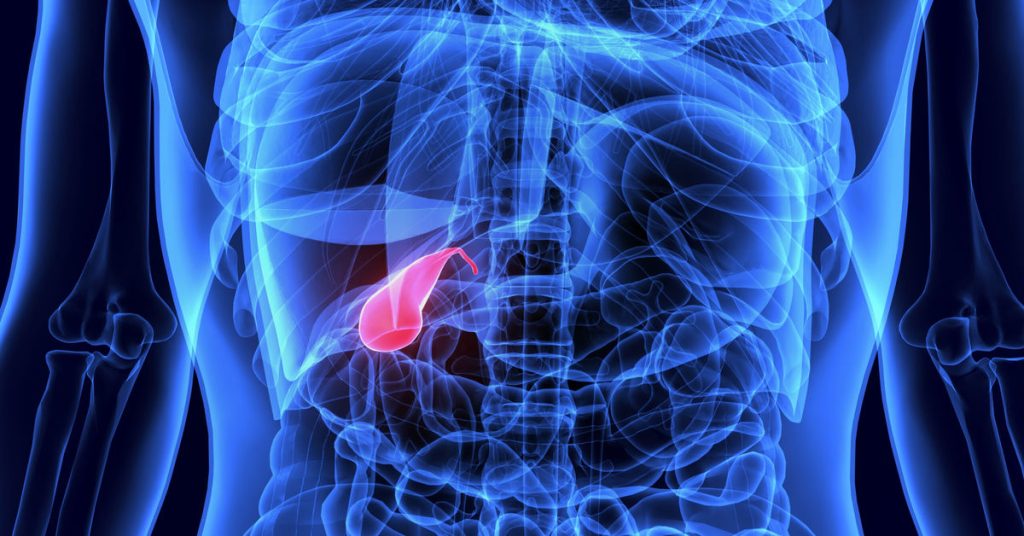

Digestive problems occur when the gallbladder becomes infected or inflamed. The gallbladder stores bile produced by the liver and sends it to the intestines during digestion. If the bile ducts are blocked by stones or obstructions, this can lead to increased pressure in the gallbladder and inflammation. Gallbladder inflammation It is usually characterized by a sudden onset and severe abdominal pain.

The gallbladder stores bile, which helps break down fats during digestion. However, in some cases the flow of bile can be blocked. Usually gallstones block the duct and pressure builds up in the gallbladder. Over time, this leads to inflammation. The disease often presents with sudden onset of abdominal pain. If not recognized early, the infection can progress. It can cause serious health problems. It is therefore important to pay attention to the symptoms.

The gallbladder is an organ that plays an important role in the digestive system. However, in some people, bile flow can be blocked for various reasons. Gallstones are the most common cause of this condition. When the stones block the duct, the pressure in the gallbladder increases and infection may develop. This problem can occur in all age groups. However, some people are at higher risk. Therefore, knowing the risk factors helps to take early precautions.